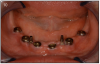

Figure 10 – Six implants placed in the lower arch with 2 mini-implants to help keep denture stable

As stated earlier, dentures replace only about 10% of chewing function. This causes digestive problems, due to an inability to chew food properly, also leading to malnutrition, due to an increase in consumption of softer, more processed foods. This inability to chew also results in atrophy of the alveolar arches due to lack of adequate pressure on the bone. When the denture is pressing on the mental foramen, then patients will experience pain and numbness of the lower lip. A good solution for these denture wearers is to place 2 to 4 implants in the mandible to stabilize the denture. The denture is then attached to the implants via snap-on attachments or a bar. (Figures 13A-C) According to the 2002 McGill Consensus Statement on Overdentures, mandibular two-implant overdentures are superior to conventional dentures in all clinical trials, even up to nine years in function.32